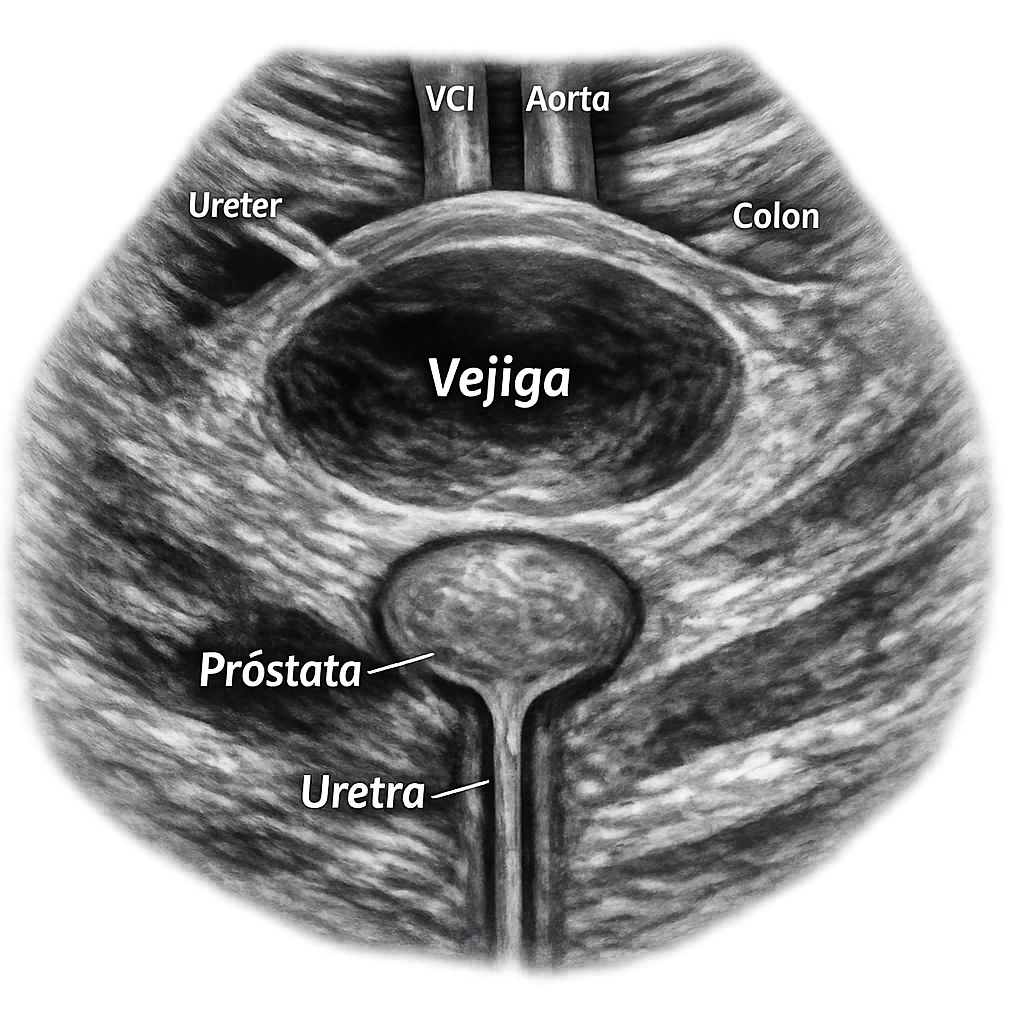

Aquí encontrarás imágenes detalladas que ilustran exploración de órganos abdominales sanos y con patologías en perros y gatos.

Aprende los fundamentos para interpretar imágenes ecográficas de órganos abdominales.

Analiza ecografías con patologías para un diagnóstico preciso y detallado.